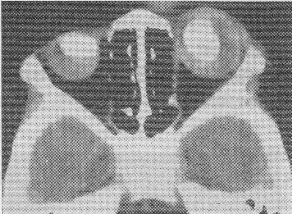

男孩,2岁,双眼疼痛1年,右侧眼球突出。CT平扫如图:![]() |

| 正确答案:3.A;4.D 解题思路:视网膜母细胞瘤是儿童眼球内最常见的恶性肿瘤,多见于3岁以下的幼儿,多数为单眼发病,约1/4的病人双眼发病,CT表现为眼球内实性肿块,若伴有斑块或斑点状钙化则较具特征。肿瘤较大致眼球增大、突出。视网膜母细胞瘤为起源于视网膜的胚胎性恶性肿瘤。 |